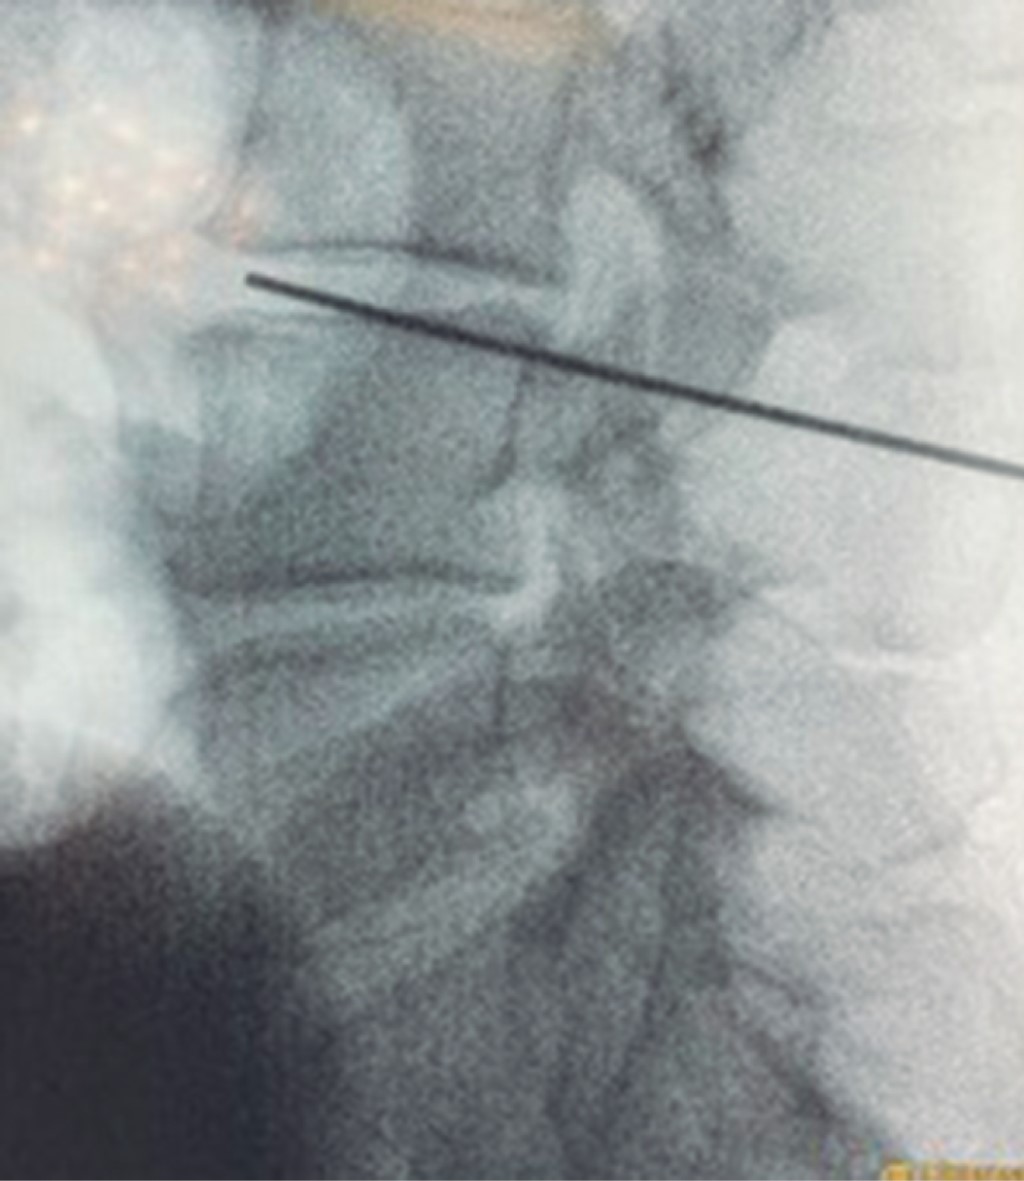

Figura 1